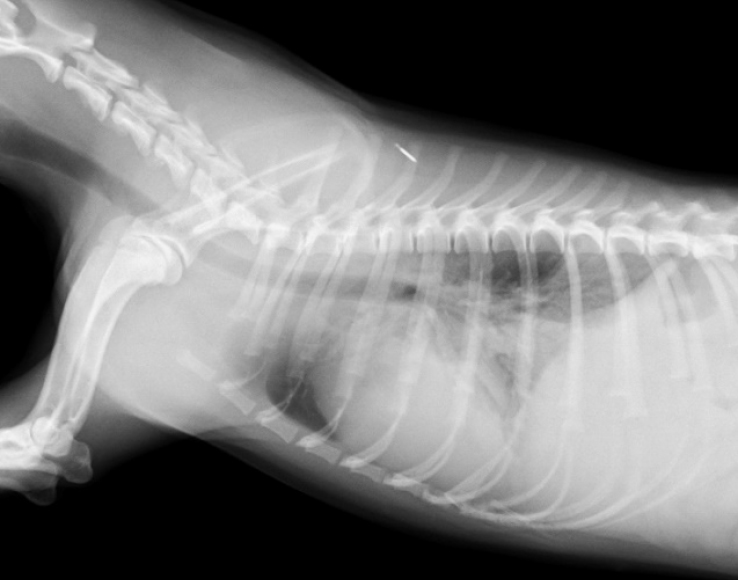

レントゲン検査によって肺や気管の状態を確認することができます。肺野の病変の画像パターンを分類し、どのような疾患が疑わしいのか診断することができます。また、吸気時と呼気時のレントゲン写真を撮ることによって、気管虚脱の有無を診断することができます。当院では、単純なレントゲン撮影では判断の難しい気管虚脱に対しても透視下のレントゲン撮影が可能であり、動的に気管虚脱を診断することができます。超音波検査は、胸水や腫瘤の診断に役立ちます。また、呼吸器症状の原因となりうる心臓疾患の存在を診断することができます。